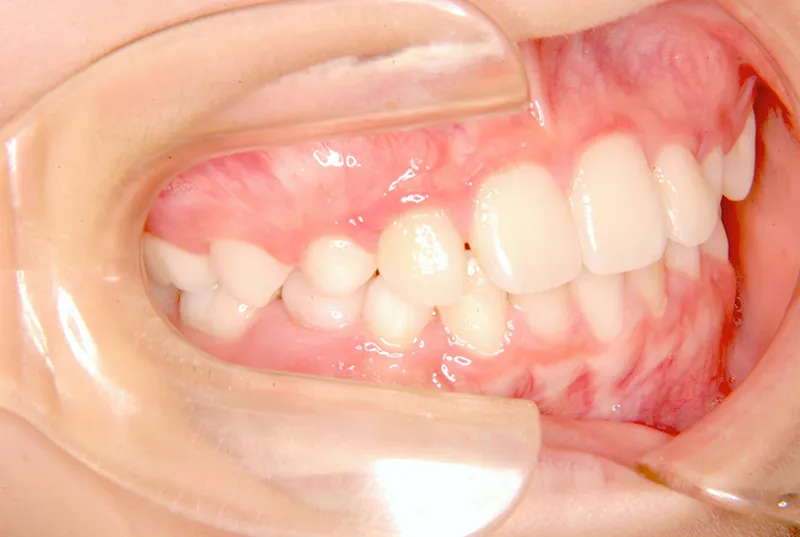

• 初診

治療終了後

初診時年齢 小学校1年生 (男性) 主訴 すきっ歯・ガタガタ・受け口

診断名 叢生・反対咬合・空隙歯列 装置名

拡大床

特徴 ゆがんで生えている

状態 永久歯が生える隙間がない(叢生)

受け口(下顎前突/反対咬合)

すきっ歯(空隙歯列)

上の前歯が下の前歯より後ろに入って、受け口になっています。

下の歯は永久歯の生えるスペースがないので、オリジナル矯正装置で受け口を治して、永久歯の生えるスペースを作りました。

治療回数19回、2年5ヶ月の治療期間で矯正治療を終了しました。

主訴が改善され、ご満足頂きました。

初診